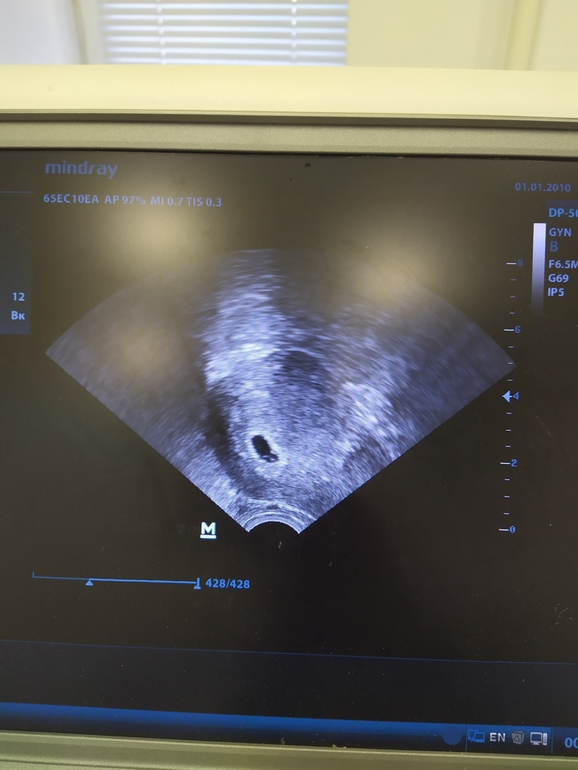

Lar Bear 5 лет Мое первое УЗИ Первое УЗИ 5+4 недель Посмотрите еще 20 записей на эту тему Отменить Ответить Надежда Прелесть! Поздравляю! Лёгкой вам беременности 🥰🥰🥰 29.10.2020 Ответить Год планирования и наконец получилось Чаты Беременных Выберите чат: Январята-2026 Февралята-2026 Мартята-2026 Апрелята-2026 Майчата-2026 Июнята-2026 Июлята-2026 Августята-2026